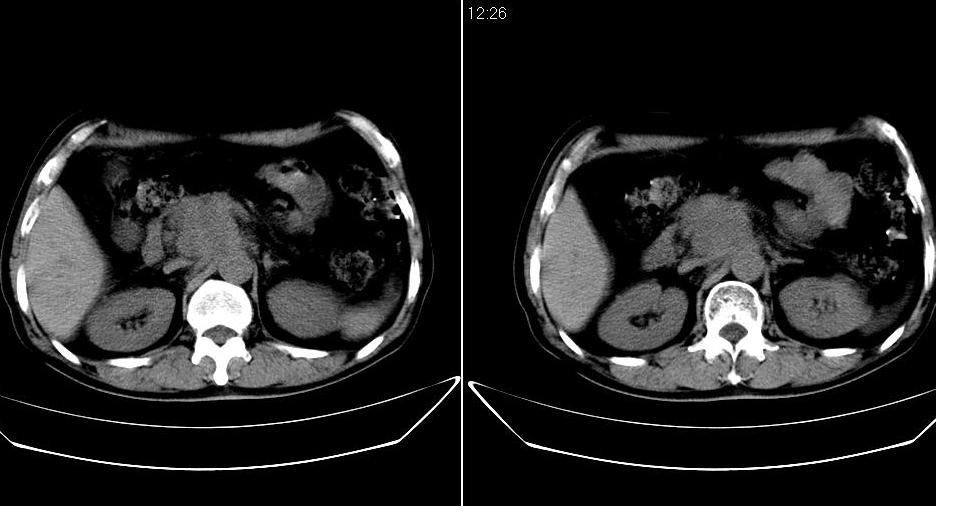

标题: CT24891:上腹部CT平扫

男 48岁,09年8月份在上级医院确诊胰头癌,准备在我院化疗。

胰头体积增大内见低密度影考虑为占位,肿瘤性病变可能性大。

胰头体积增大,外形不规则,密度欠均,支持胰头癌可能性大。